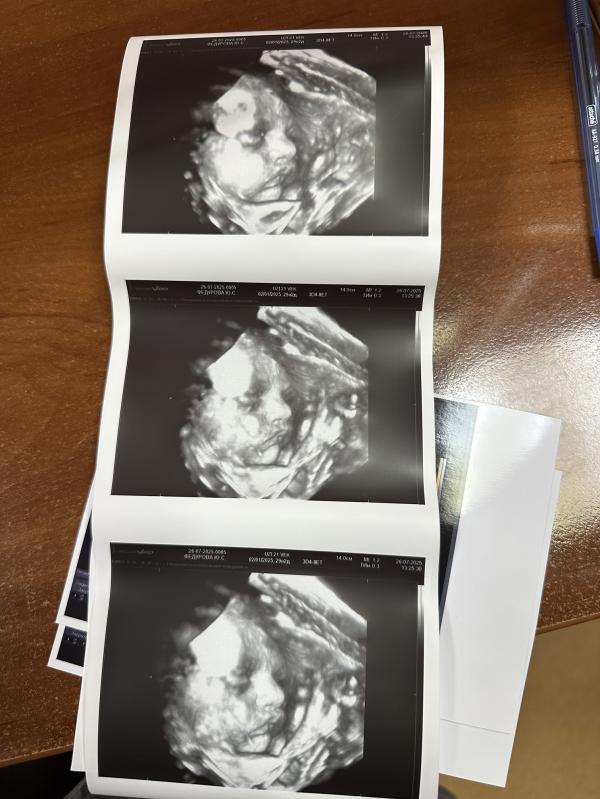

Мы там УЗИ с младшей делали)) недорого и запись хорошая) первое фото - топчик

Симпотичный малыш, вроде носиком на вас похож